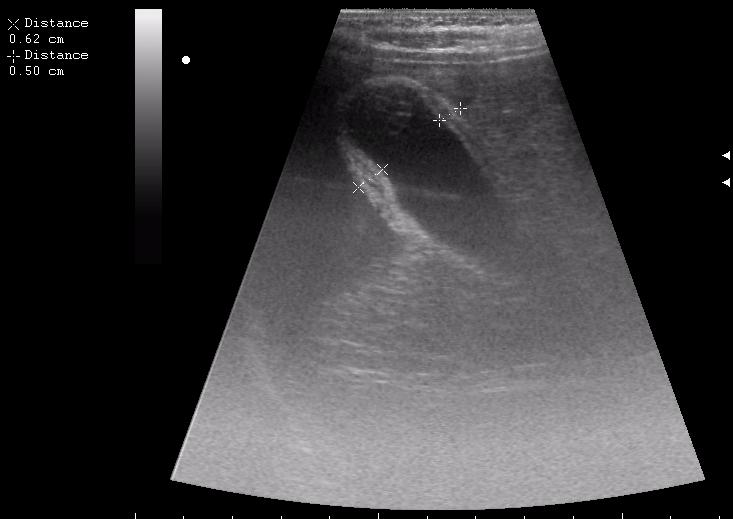

железный дрын вошел в правую подвздошную область, остановился в капсуле печени.

сегодня был селезёночный день.